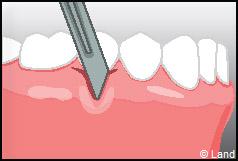

LES TECHNIQUES SANS APPORT DE GENCIVE :

Elles font appel à des lambeaux de gencive restante à proximité des récessions, qui sont déplacés et repositionnés sur la récession.